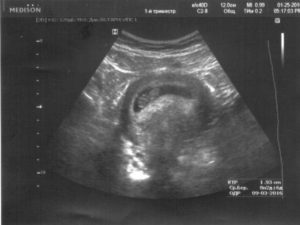

- УЗИ, определяет 8 недель беременности размер плода, состояние кровоснабжения, плаценты и т.д.;

После того как вы сообщите врачу о тревожащих вас симптомах, он назначит вам ультразвуковое исследование. Специалист, который будет делать УЗИ, сможет определить состояние плода, стенок матки. Кроме того, можно определить локализацию спазма, так, он может локализоваться на задней стенке. Не менее часто встречается гипертонус передней стенки.

Для диагностики гипертонуса используется ультразвуковое исследование, при проведении которого может быть выявлен гипертонус задней стенки матки, а также передней. Однако, этот признак не всегда может говорить об угрозе прерывание беременности. Матка может прийти в тонус в ответ на прохождение ультразвуковой волны через ее стенку.